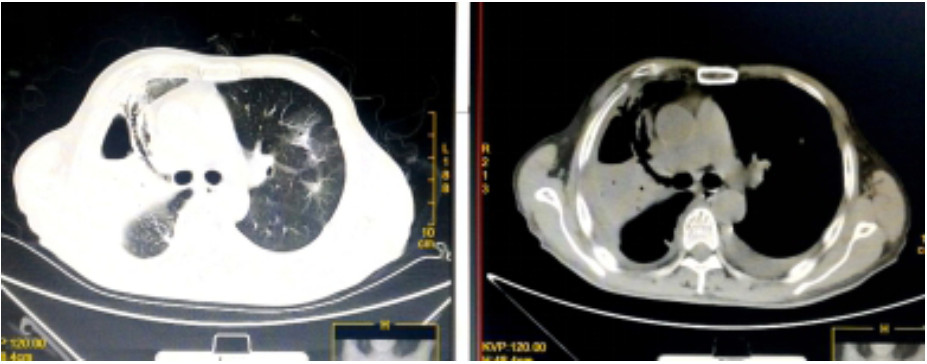

入院诊断“社区获得性肺炎”。予无创呼吸机支持(FiO2 75%),经验性予以美罗培南静脉泵入1.0 g 2次/d、磷酸奥司他韦口服75 mg 2次/d、莫西沙星静脉滴注0.4 g 1次/d。入科后治疗4 h仍无尿,且呼吸困难进行性加重,血氧饱和度进行性下降,氧合指数109 mmHg,予以经口气管插管接呼吸机辅助通气及连续性血液净化等治疗。机械通气后,吸出大量灰褐色痰,且病情进展快,短时间无法脱机拔管,12月17日气管切开。12月17日复查血常规:血白细胞2.49×109/L,中性粒细胞百分比0.925,血红蛋白70 g/L,血小板62×109/L。停用莫西沙星改用利奈唑胺0.6 g静脉滴注2次/d。12月19日胸部CT示,⑴双肺散在多发感染性病变,右侧为著;⑵右肺空腔伴气液平;⑶右侧胸腔积液(图 2)。12月19日血白细胞3.7×109/L,中性粒细胞百分比0.882,淋巴细胞百分比0.098,血红蛋白78 g/L,血小板115×109/L,入科后立即送检的血、痰培养回报均阴性。12月20日肺泡灌洗液病理回报镜下见炎症细胞、吞噬细胞及菌丝样物,未发现恶性细胞(图 3)。12月21日痰宏基因组学检测回报:肺炎链球菌(序列数113 916)、屎肠球菌(序列数1 307)、铜绿假单胞菌(序列数16)。12月20日及24日肺泡灌洗液、血培养均回报为屎肠球菌,药敏试验结果示,对氨苄青霉素、环丙沙星、红霉素、庆大霉素、青霉素耐药;对替考拉宁、替加环素、利奈唑胺、万古霉素、奎奴普丁/达福普丁敏感。继续利奈唑胺600 mg 2次/d,总疗程62 d。治疗期间血红蛋白在66~91 g/L,血小板均在(100~300)×109/L。12月26日CT引导下经皮肺组织穿刺术,并送检病理细胞学及组织培养,结果显示符合炎症性病变改变,病原学阴性。2020年1月9日脱离呼吸机,1月14日转入普通病房,1月23日拔出气管切开套管,2020年2月13日复查胸部CT病灶有所吸收(图 4),2月24日好转出院。出院半年后电话随访,当地医院复查胸部CT示病灶较前明显吸收,已经正常工作。

图 4 2020年2月13日胸部CT结果(双肺多发异常密度,右侧为著伴右肺空洞,较前有所吸收;双侧胸腔积液,右侧较前有所减少,左侧较前稍有增多)